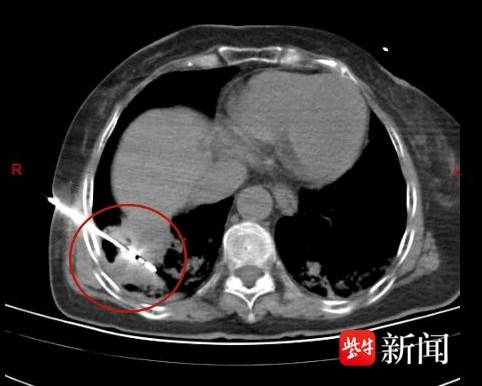

影像图

“这是一次高难度的挑战。”谭主任解释,难点不仅在于肿瘤尺寸大,更在于其位置极其“刁钻”——肿瘤已紧密粘连胸腔壁,并且顶端紧抵膈肌。手术中最大的风险在于可能损伤胸膜,导致胸膜瘘,进而引发气胸(肺部萎缩);同时,消融能量控制不当还可能产生肺空洞。这要求主刀医生既要具备“GPS”般的一次性精准穿刺能力,避免反复穿刺损伤胸膜,又要像手握“精密温度计”一样,精准控制消融范围,彻底摧毁癌细胞的同时,最大限度保护周围的健康组织。